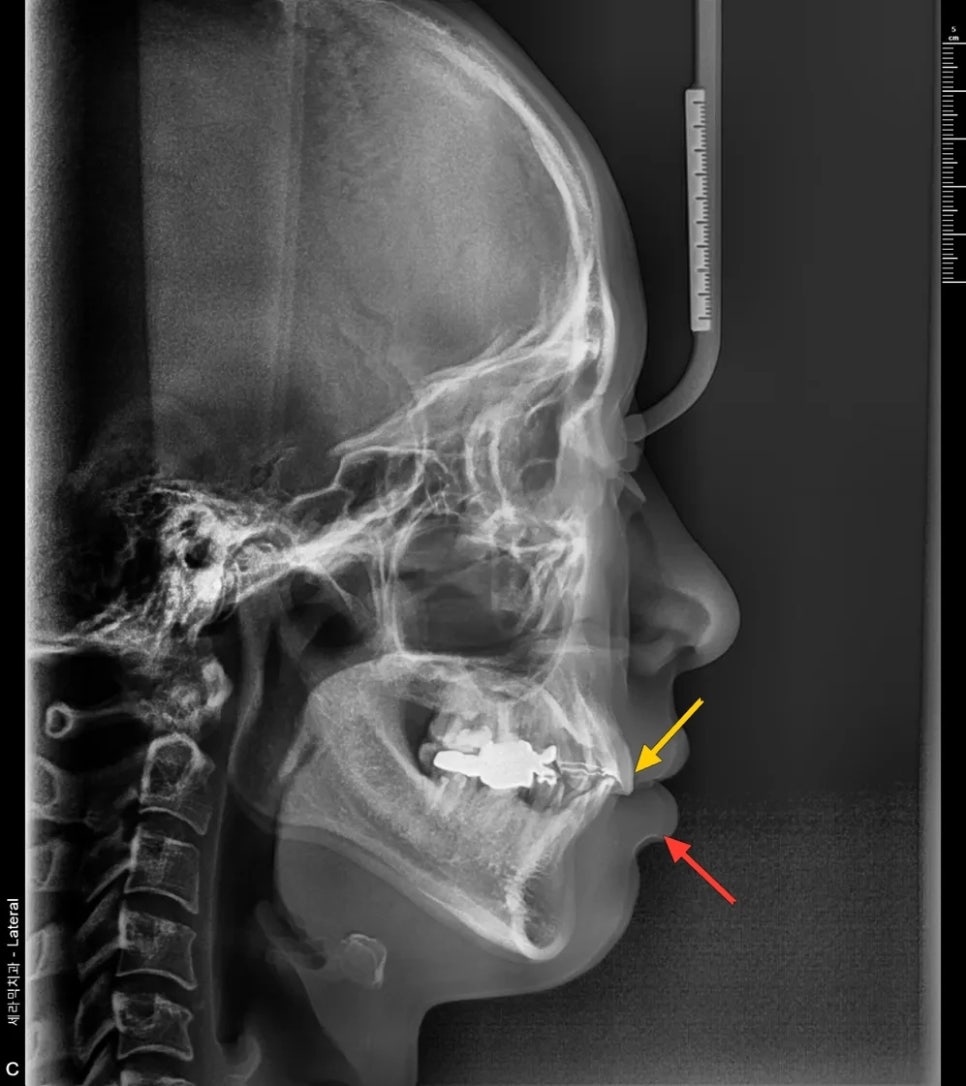

측면 엑스레이 분석

측면 두부 방사선 사진을 분석해 보니, 윗앞니가 아랫입술을 누르면서 입술이 말려나오는 양상이 확인되었습니다. 쉽게 말해, 윗앞니가 앞으로 나와 있어서 아랫입술을 밀어내고 있었던 것입니다. 이 말은 곧, 윗앞니를 뒤로 넣으면 아랫입술도 자연스럽게 뒤로 들어올 수 있다는 의미이기도 합니다.

윗니(노랑)가 아랫입술(빨강)을 밀어내고 모양새가 확인됩니다